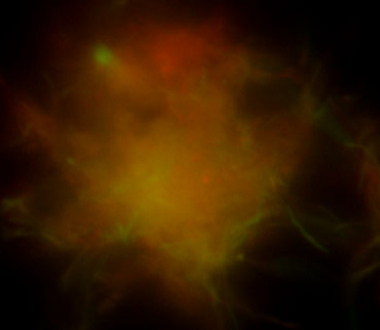

One of Dr. Ojha’s projects is based upon the hypothesis that the extraordinary persistence of M. tuberculosis against antibiotics is facilitated by the pathogen’s ability to grow in organized, multicellular structures called biofilms. His laboratory has developed various molecular tools to visualize the location of drug tolerant “persisters” inside the biofilms, and using these tools, is asking how, over time, localization and concentration of these “persisters” can be perturbed.